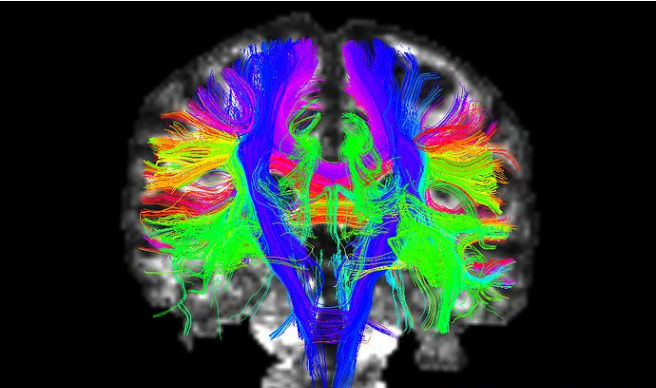

二、DTI数据分析

TBSS分析以及纤维追踪分析.可构建结构脑网络,利用图论的方法来研究脑网络的复杂网络指标,比如:小世界属性(small world),rich hub,聚类系数,最短路径等各种图论指标。

Figure 2.白质纤维追踪 Figure 3. TBSS